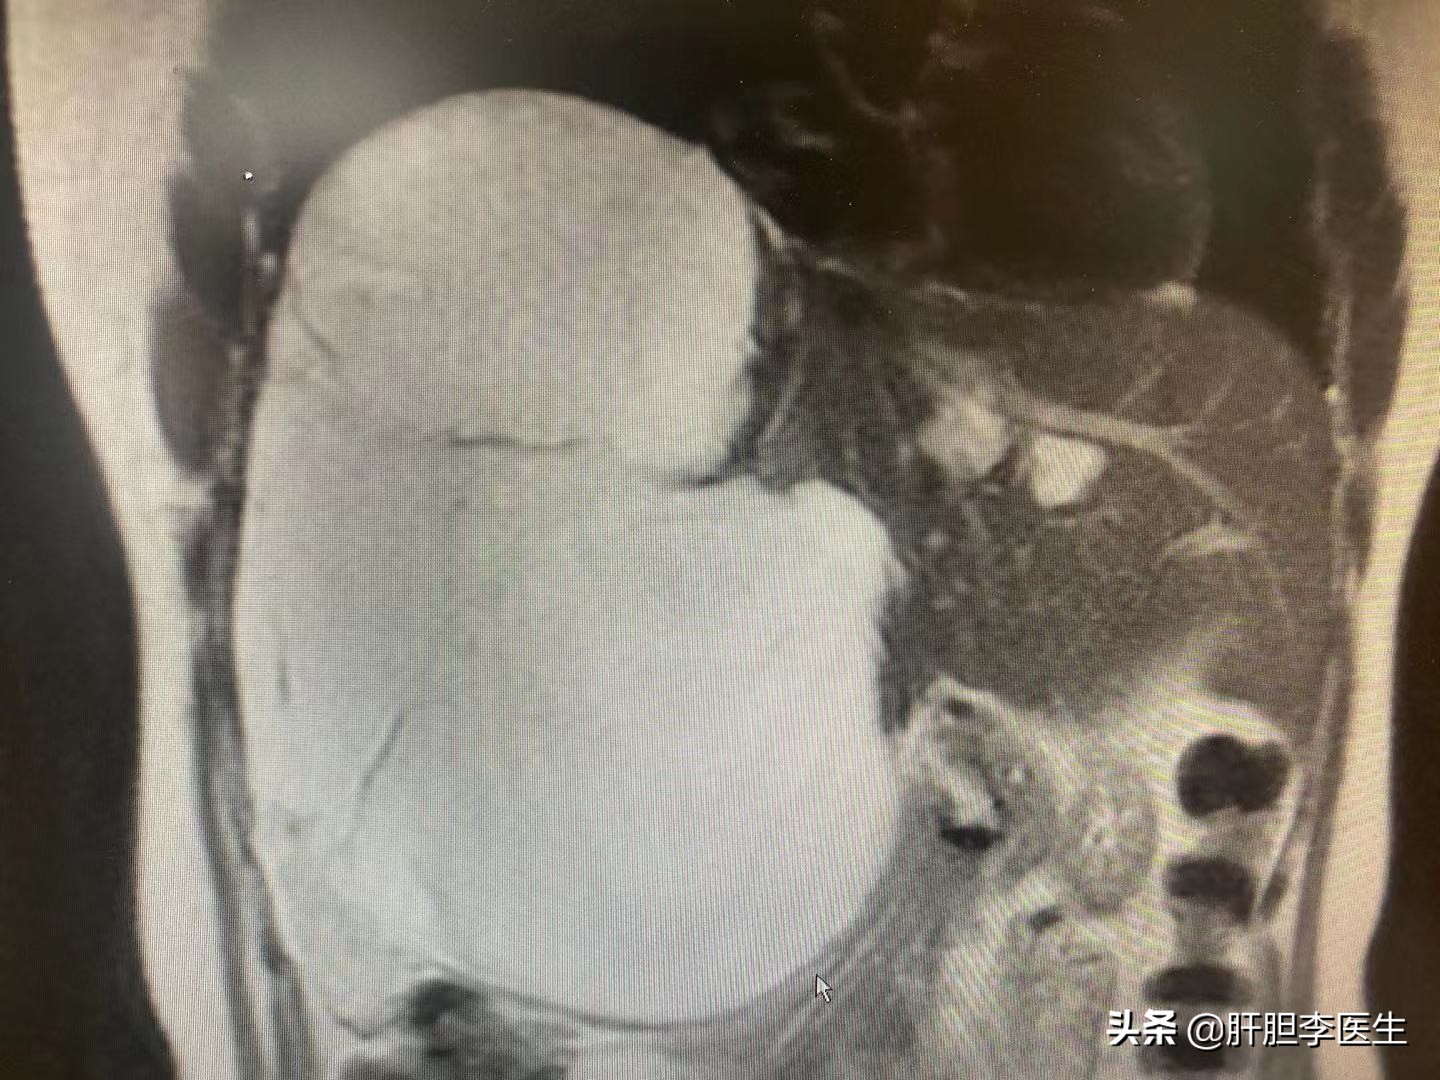

这次来复查的时候,直接做了肝脏的增强核磁,虽然知道血管瘤会增大,但是没想到看到片子的时候还是有点出乎意料,血管瘤的最大直径已经达到了17cm,几乎右边的肝脏都是血管瘤了,只剩下左边半个肝脏在维持正常工作了。当然手术的风险并不止这一点,而是血管瘤紧紧地贴在下腔静脉上,手术切除血管瘤就要把血管瘤从下腔静脉上一点一点地扒下来,在这个过程中随时有可能出现大出血的情况,而且下腔静脉的出血非常凶险,可能会有生命危险。